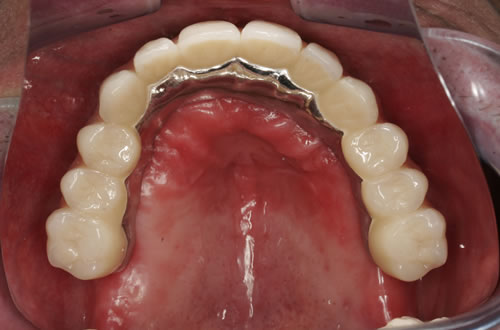

Für den zahnlosen Ober- und Unterkiefer werden dies häufiger Stegkonstruktionen oder Teleskopversorgungen sein (Abb. 8.8 bis 8.16).

Abb. 8.10: Individueller Stahlsteg auf 4 Implantaten im zahnlosen Oberkiefer.

Abb. 8.11: Eingegliederter graziler, herausnehmbarer, gaumenfreien Zahnersatz.

Abb. 8.12: Zahnloser Oberkiefer mit 8 Implantaten und eingesetzter Unterkonstruktionen.

Abb. 8.13: Abnehmbare, grazile Brücke.

Auch eine festsitzende zementierte oder verschraubte Brücke ist möglich (Abb. 8.17 bis 8.19). Hierbei muss eine günstige Lachlinie vorliegen und der Kieferschwund sollte noch nicht zu weit fortgeschritten sein. Die Zähne würden sonst sehr lang wirken, da die Zahnpositionen in die ehemalige Position der Zähne zurückgebracht werden muss. Langes Prothesentragen und entsprechender Knochenverlust erschweren besonders im Oberkiefer festsitzenden Zahnersatz. Sehr exakte Voruntersuchungen und präzise Implantatpositionen mit entsprechenden Knochenaufbaumaßnahmen sind häufig notwendig, um den Patienten diesen Wunsch zu erfüllen.

Abb. 8.17: Verschraubte Brücke auf Implantaten im zahnlosen Oberkiefer (Modellansicht).